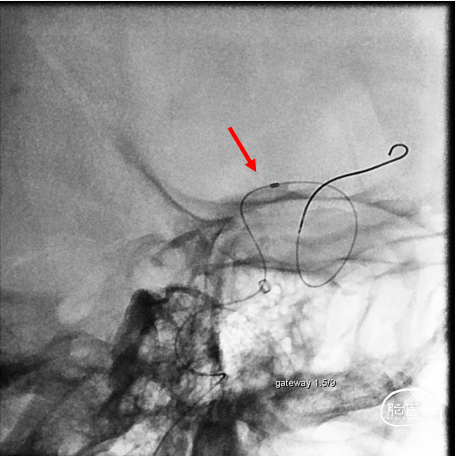

交换3m Floppy,Gateway 1.5mm/9mm,6atm

支架打开不良